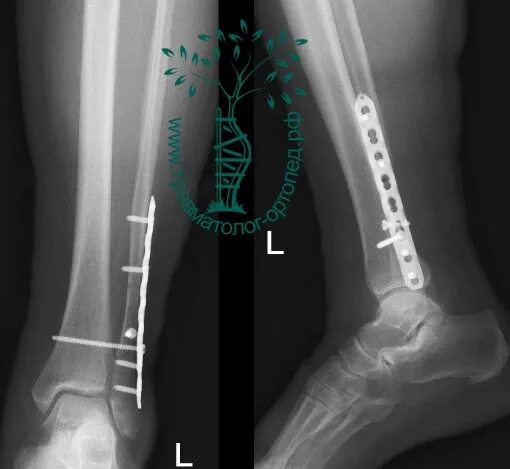

Лодыжка перелом смещение операция пластина